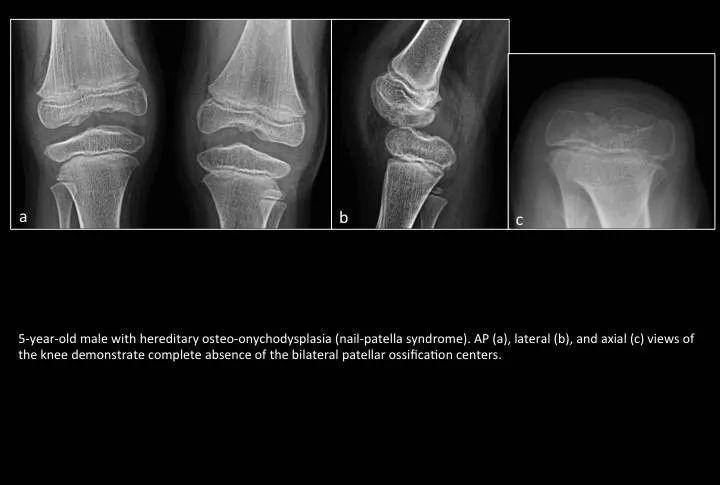

Fig. 4: Patellar aplasia

图4:髌骨发育不良

5岁男孩遗传性指(趾)甲-髌骨综合征(nail-patella syndrome)